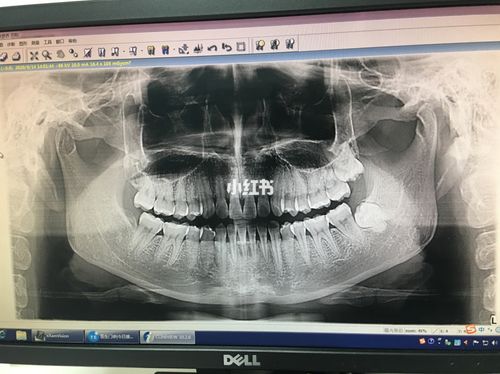

颚阻生牙是指牙齿在生长过程中受到障碍,无法正常生长到口腔中。这种现象可能由多种因素引起,包括牙齿排列不当、缺乏足够的空间、牙齿生长方向错误等。在一些情况下,颚阻生牙可能会导致其他牙齿移位或咬合问题。

颚阻生牙和智齿之间并没有必然的关系。尽管智齿是最后一颗长出来的牙齿,但它并不一定会引起颚阻生牙。实际上,颚阻生牙可能会影响任何一个牙齿,而不仅仅是智齿。

处理颚阻生牙的方法取决于牙齿的位置和严重程度。在一些情况下,牙医会建议拔除颚阻生牙。在其他情况下,可能需要进行正畸手术或其他治疗来解决问题。